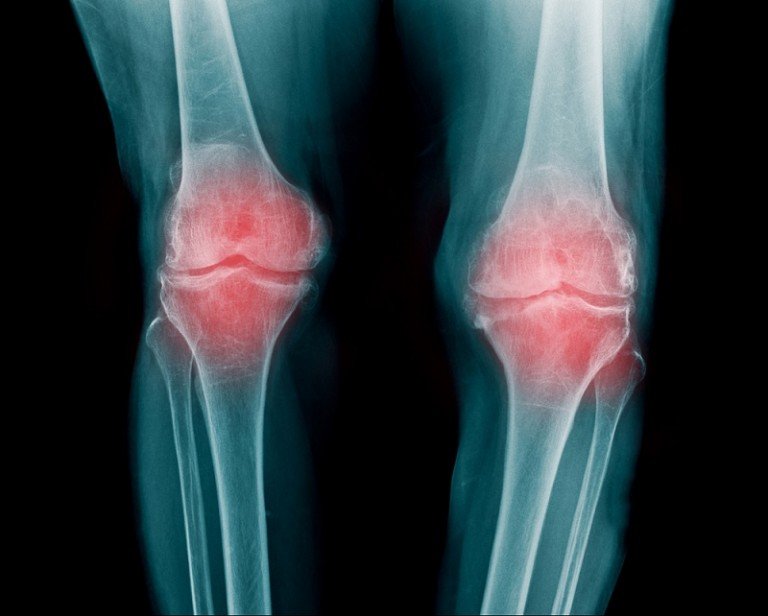

שחיקת סחוסים היא אחת הבעיות הרפואיות הנפוצות ביותר, ואנשים רבים צפויים לסבול ממנה במהלך חייהם. שחיקת סחוסים מופיעה במפרקים שונים בגופינו, ובעיקר במפרק הברך ובמפרק בירך. אז מהי בעצם שחיקת סחוסים? מהן הסיבות לתופעה? איך מאבחנים אותה ומהם הטיפולים? מוזמנים לקרוא במאמר שלפניכם. מהו תפקיד הסחוסים בגופינו? בגוף האדם ישנם מספר מפרקים – נקודות חיבור … המשך לקרוא שחיקת סחוסים – שאלות ותשובות